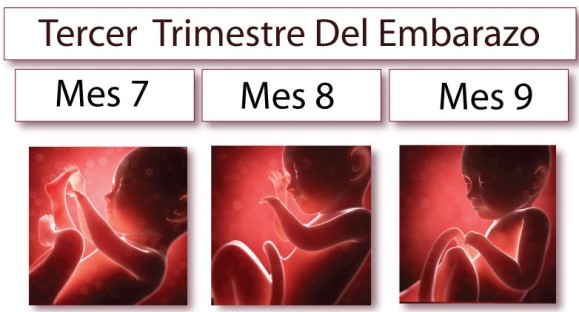

Tercer trimestre

En el tercer trimestre de embarazo, es posible que el cansancio vuelva a aparecer debido a que el organismo tiene que hacer un gran esfuerzo para atender las necesidades del bebé y cargar con el peso extra. El útero y el vientre empiezan a crecer y el peso del bebé, junto a la compresión de los vasos sanguíneos de la pelvis y el abdomen, así como la restricción del movimiento del diafragma, dejan a la mujer embarazada agotada.

Además, el cansancio se incrementa porque el volumen y peso de la barriga (unos 12 kg en total) hacen más difícil dormir por las noches. No solo la acción de la progesterona en el sistema nervioso central, sino también el tamaño del útero, impiden que la gestante tenga una buena noche de sueño. La movilidad y encontrar una postura cómoda en la cama puede ser toda una aventura.

Además, la micción frecuente debida a la comprensión de la vejiga por el útero hace que la embarazada necesite levantarse varias veces por la noche, interrumpiendo el ya difícil sueño.

Los movimientos fetales y la ansiedad debida a la proximidad del parto que puede generar en la gestante ciertos miedos, inseguridades, etc. pueden originar problemas para dormir durante el embarazo.